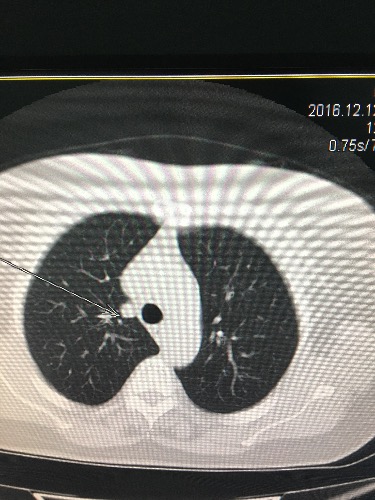

CT52450:咳嗽二个1月

右上肺主气管旁结节灶

右上肺主支气管旁可见结节。考虑:右上肺占位可疑。建议增强。

图像太少无法诊断。